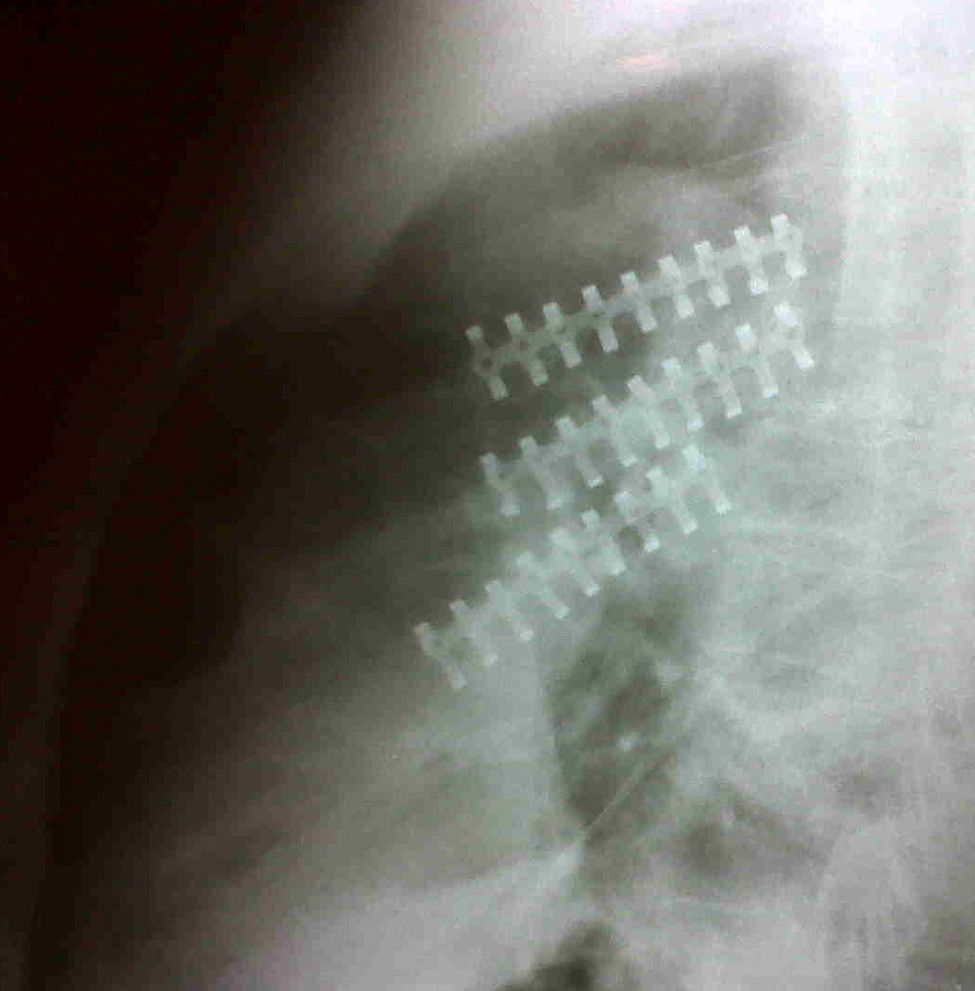

Clinical casesCase 161-Year-old male patient with a history of chest blunt trauma caused by being run over by a bull. He was transferred to an emergency department where he went into respiratory failure; he was intubated and needed mechanical ventilation. During the initial assessment, a large deformity was identified in his left anterior thoracic wall with unstable thorax associated with subcutaneous emphysema. The chest X-ray registered a left-sided pneumothorax, so a left-sided closed thoracotomy was performed and the patient was transferred to the intensive care unit. At this point, a chest computerised axial tomography scan was ordered, which evidenced multiple displaced left rib fractures and pneumothorax (Fig. 1). With these findings, a cross-consultation with thoracic surgeons was made, who considered that the patient was a candidate for rib osteosynthesis with an 8-hole, one-third tubular osteosynthesis plate with bicortical screws. This procedure was carried out without complications, and watertight closure was used after surgery (Fig. 2).

The patient was extubated six days after surgery and discharged 14 days after surgery, without complications. He returned to work 30 days after the trauma. There was no pulmonary function follow-up since the patient was lost.